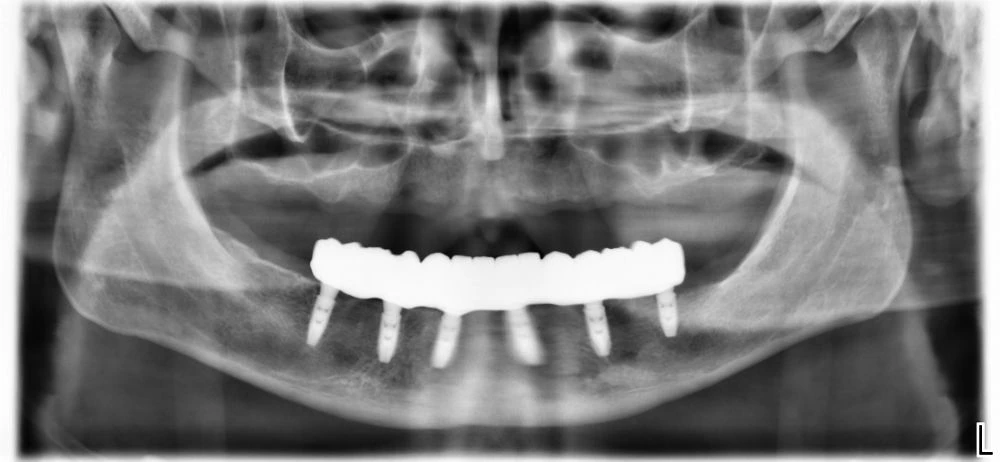

RO Цирконий – постоянна конструкция

/ Липсва слабата сянка на порцелана. Вижда се хомогенната сянка на Циркония/